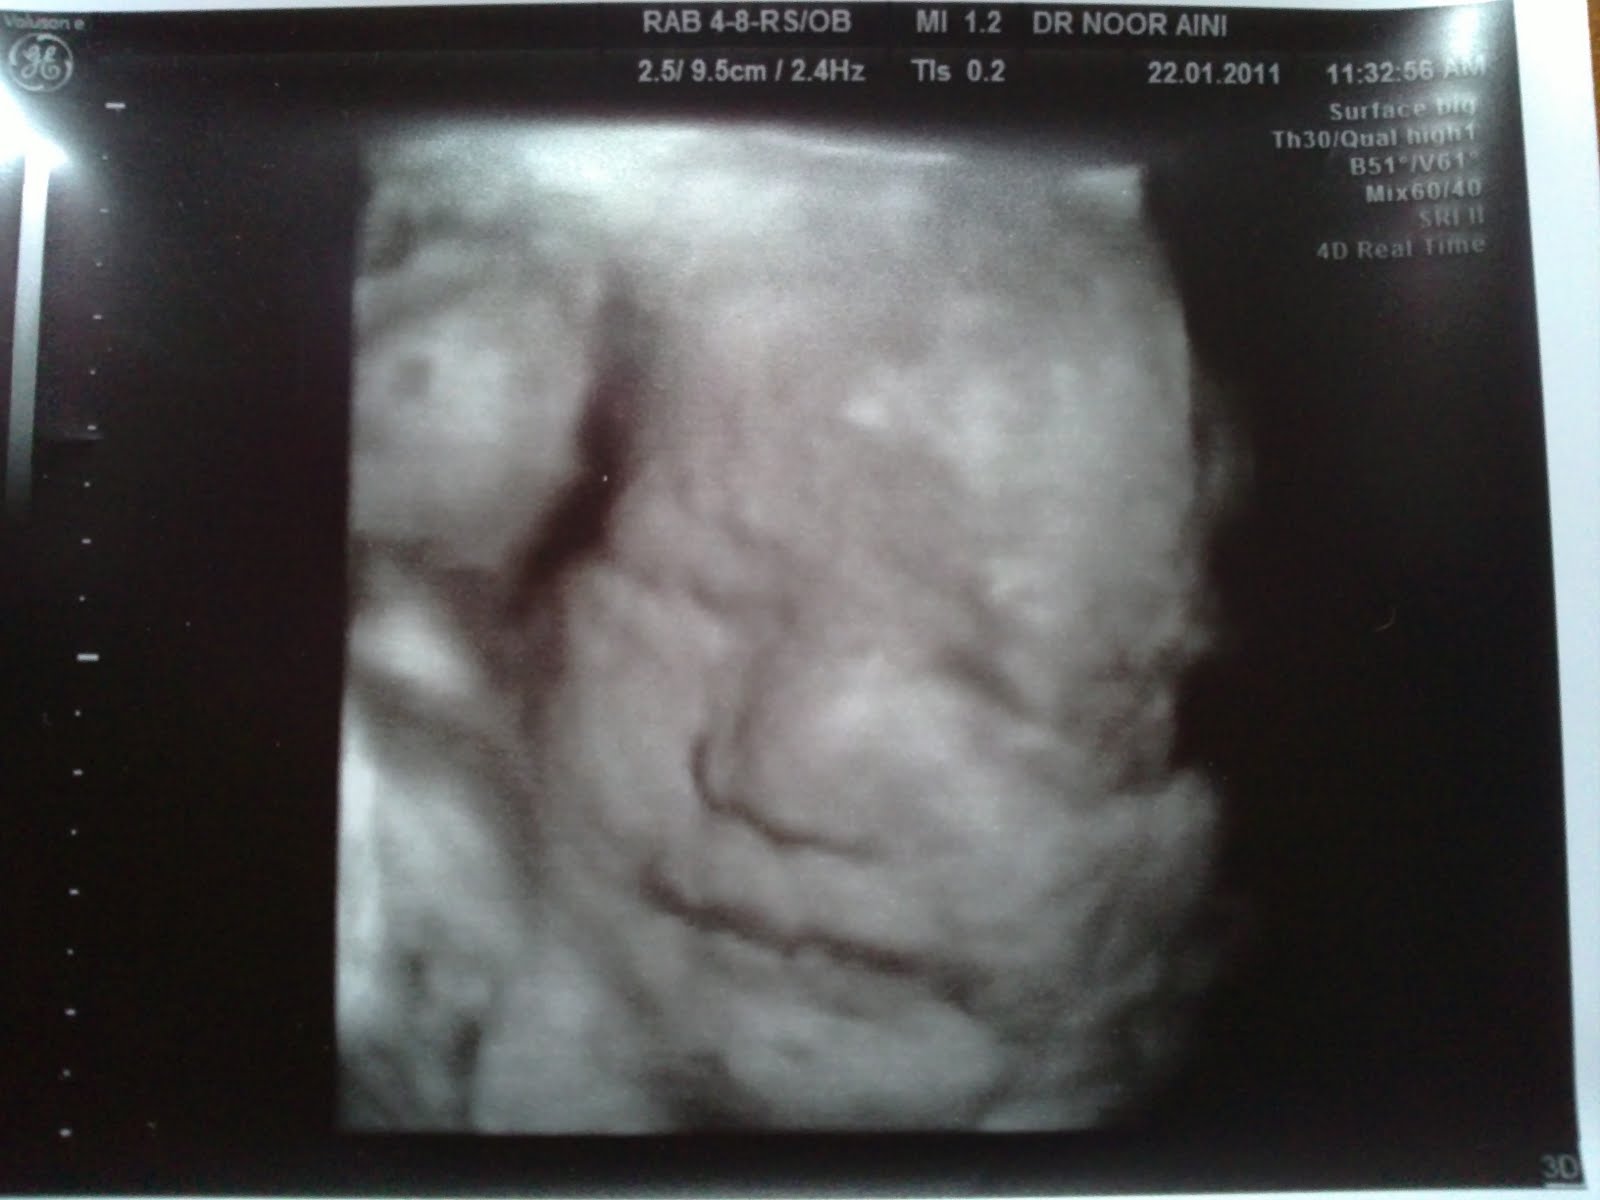

32week 私人产检

由于上次被医生放了飞机

等了很多很多

终于有机会看dr nooraini了

book了星期六早上 ...

你的王子好可爱,照片照得很清楚,嘴巴很像你。

还会对你微笑,很可爱~~~

小涵熙(这次名字没有打错了吧 )微笑的那张,

感觉上很像他爸爸哦~

但是他的嘴唇很像你 |